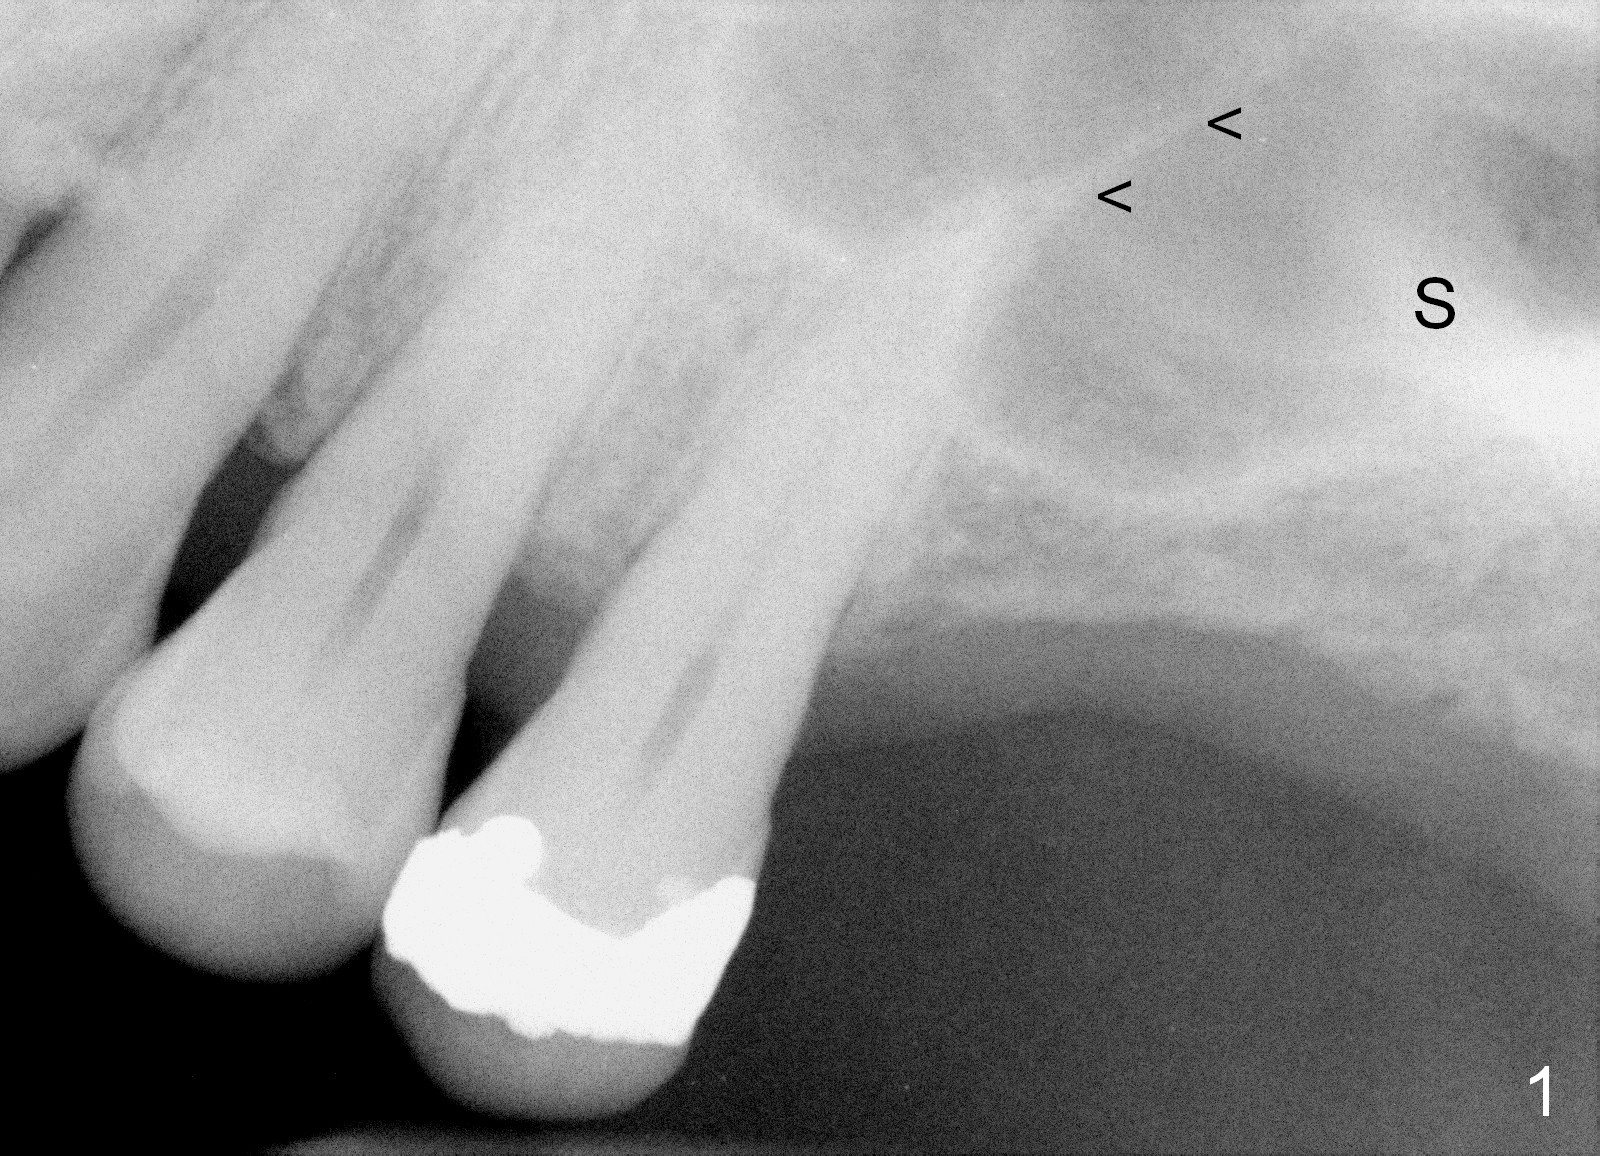

A 60-year-old man requests implant at the site of #14 (Fig.1,2, opposing a natural tooth (Fig.7)). Although bone height is limited, bone density appears high with sinus septi (S and arrowheads). The ridge seems to be wide clinically; implant will be as wide as possible. An envelop incision will be made to get the best visibility (as compared to tissue punch). At entry point, the bone height is 2.5 mm (Fig.3 red line); as the implant or osteotomy diameter increases, bone contact enhances (pink lines). If lateral window approach is adopted, a longer implant will be chosen (14 mm in Fig.3 vs. 11 mm in Fig.4, both tissue-level). The stronger distal septum may deviate the apical portion of the longer implant (Fig.3 arrow).